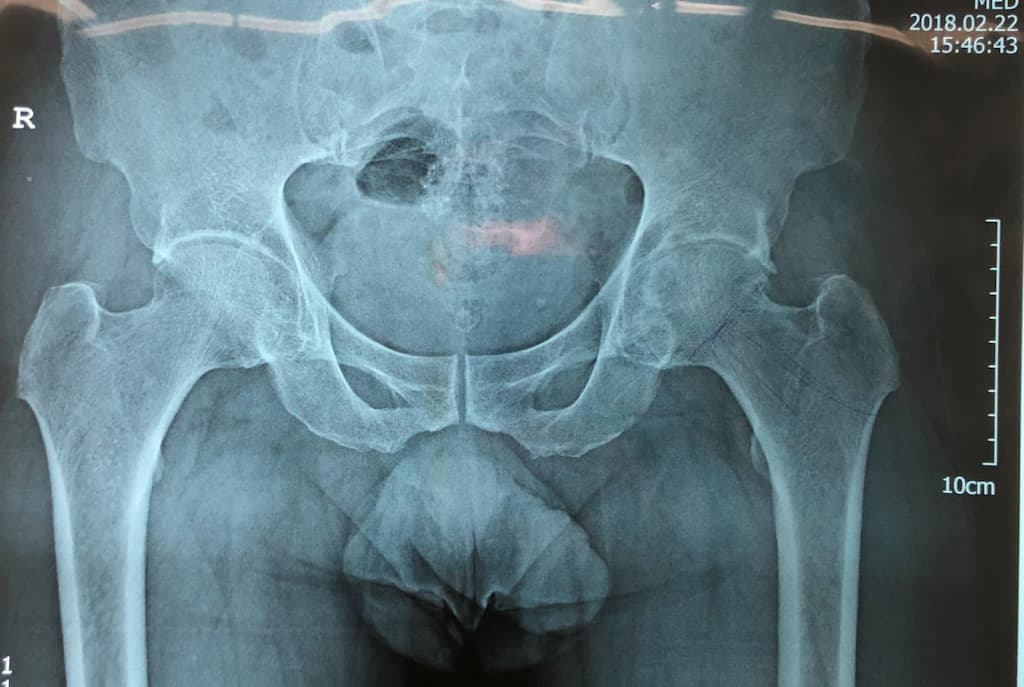

Түнхний үе солих мэс засал гэж юу вэ image3

Мэс заслын өмнөх болон дараах рентген зураг

Дунд чөмөгний толгойн үхжил

Тодорхой шалтгааны улмаас дунд чөмөгний толгойд очих цусан хангамж алдагдаж, толгойн хэсэг тэжээлгүй болсноор дунд чөмөгний толгой нь үхжилт бүхий өөрчлөлтөнд ордог түгээмэл эмгэг юм.